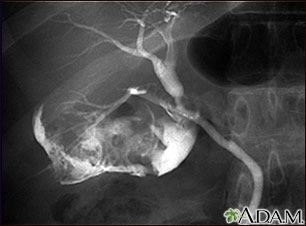

Gallbladder disease can be seen on a cholangiogram. Radio-opaque dye is used to enhance the x-ray. Here, multiple stones are present in the gallbladder (choleolithiasis). For most patients, ultrasound has replaced these older x-ray dye tests for imaging the gallbladder.